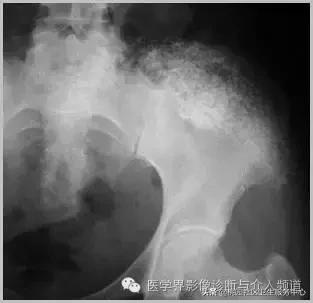

4、痛风石

为尿酸盐沉积形成,发生在关节周围软组织、包括韧带、肌腱、滑囊,眼、耳、鼻、喉、皮肤, 50%的钙化为X线平片可见。

痛风石,可见软组织肿胀及钙化灶。